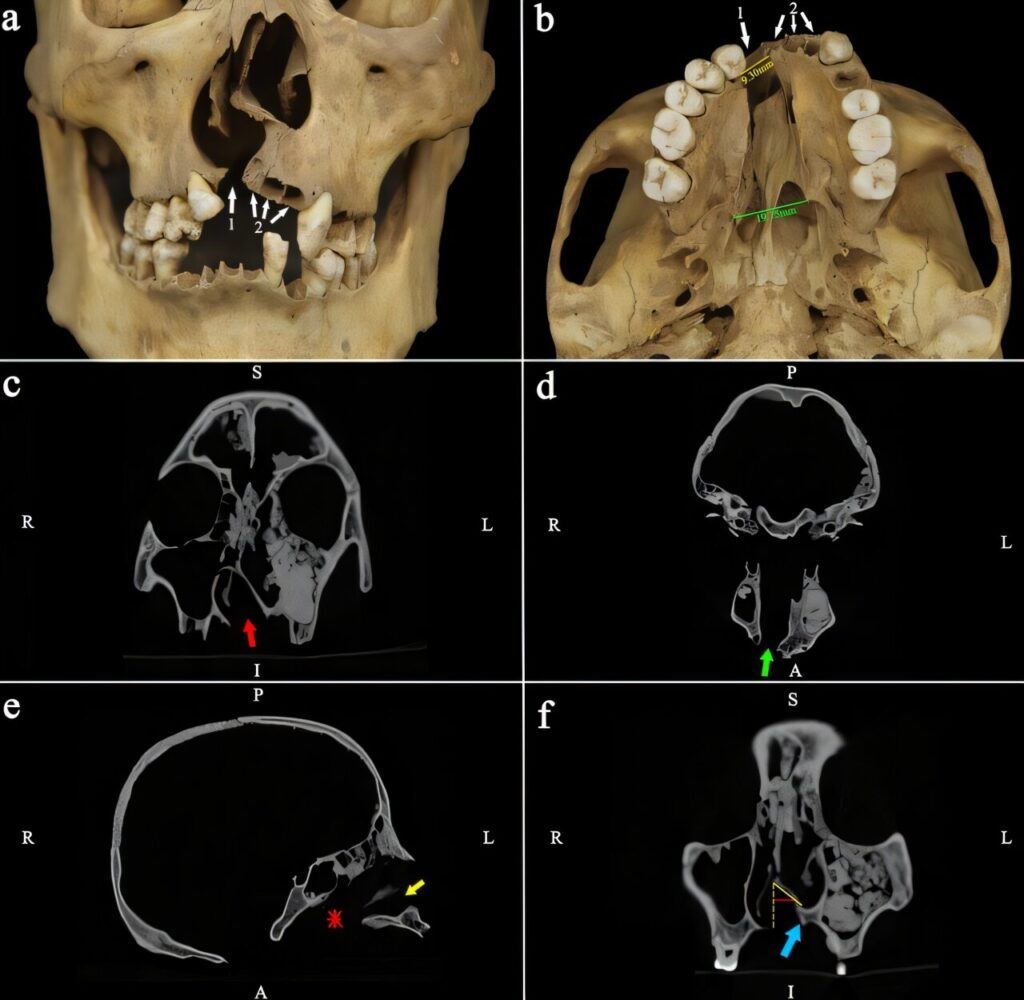

The discovery took place at the Wenchi cemetery in Shanxi Province, a site that researchers believe represents a stable, middle-socioeconomic stratum of society. Led by Dr. Xiaofan Sun, a team of scientists uncovered the remains of an individual designated as M234-2 within a well-constructed brick tomb. Through a combination of macroscopic observation and CT analysis, the researchers identified a suite of developmental defects that pointed toward a significant medical condition. The young man possessed a deformed palate, a missing upper incisor, and a severe deviation of the nasal septum.

After a rigorous process of elimination—comparing the skull to others in the same cemetery and ruling out potential causes such as physical trauma or chronic infection—the team concluded that the individual had been born with an orofacial cleft. This condition, often referred to as a cleft lip or palate, occurs during fetal development when the tissues of the lip or mouth fail to fuse correctly. In the context of the Jiaqing era of the Qing dynasty, which spanned from 1796 to 1820, such a diagnosis would have presented immediate and daunting challenges for both the child and his caregivers.

The survival of an infant with a severe orofacial cleft into late adolescence is a testament to the dedication of his family. These defects often result in profound difficulties with eating and speaking, which in many ancient contexts led to high mortality rates due to malnutrition or neglect. However, the analysis of M234-2 provided no evidence of the skeletal markers typically associated with nutritional deficiencies or chronic systemic stress. This suggests that from the moment of his birth, the young man received sustained, high-quality care that allowed him to maintain a healthy physical state despite his mechanical difficulties with feeding.